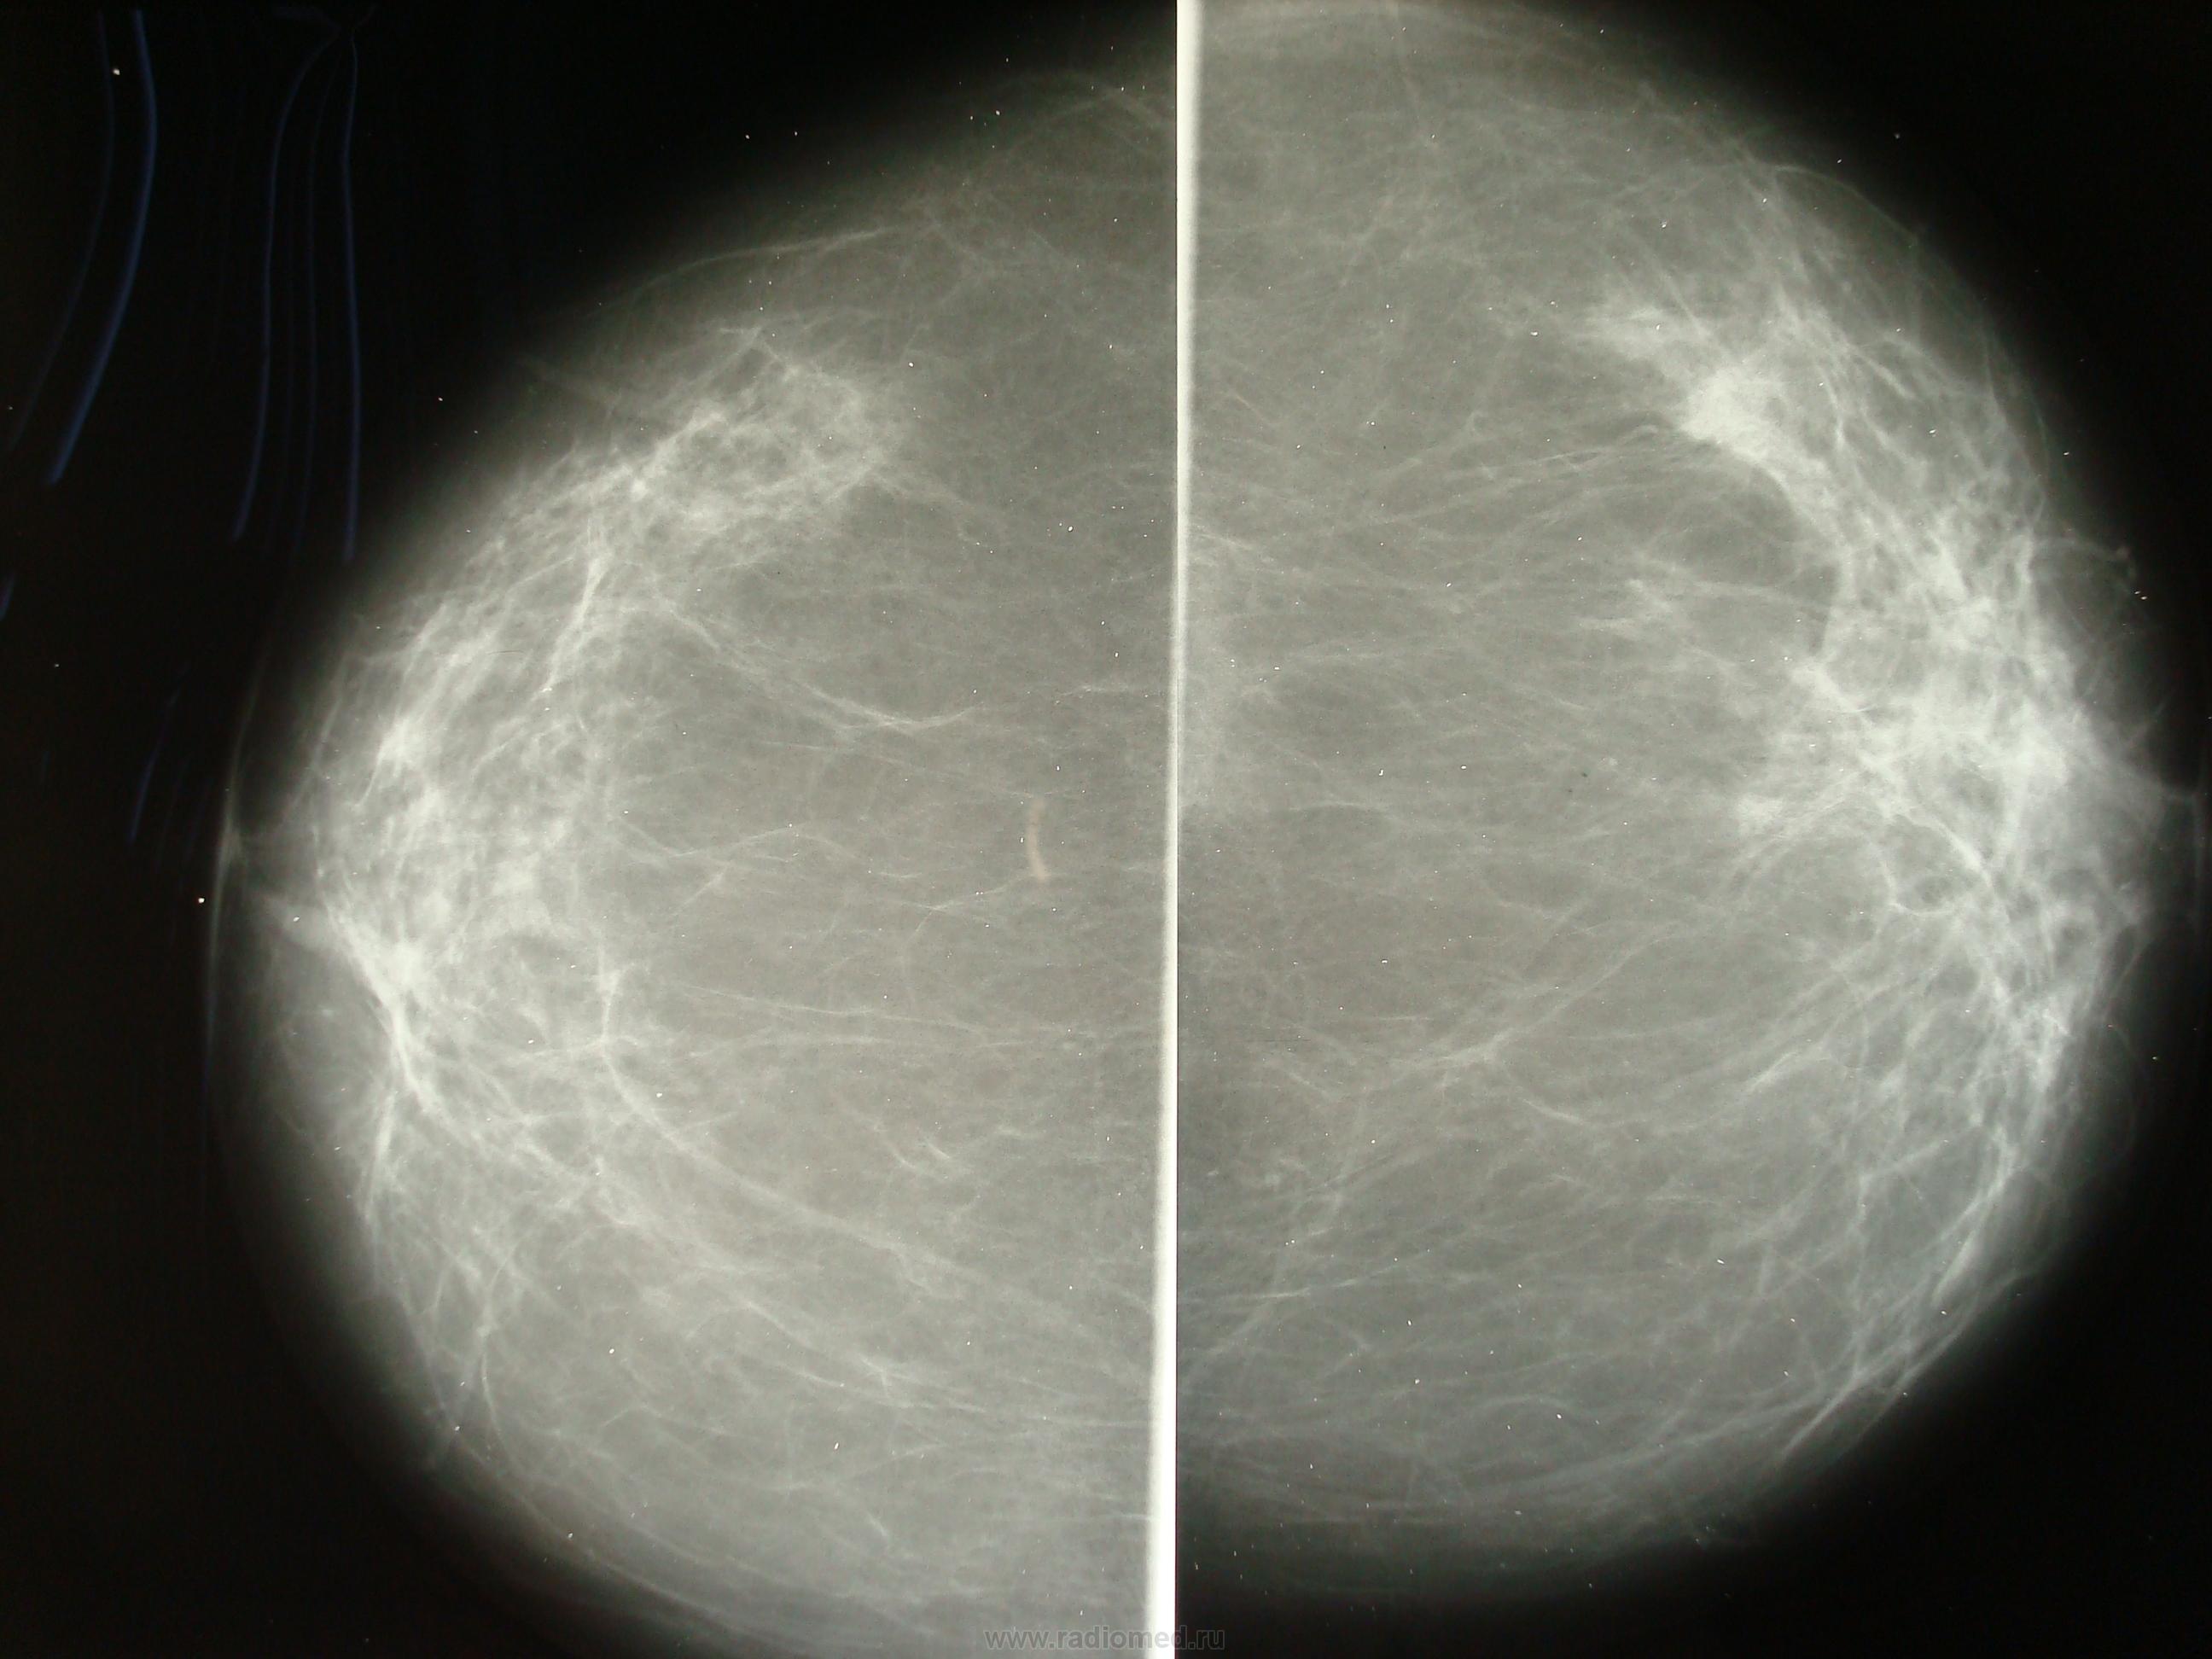

Что такое маммография: важность, процесс и результаты